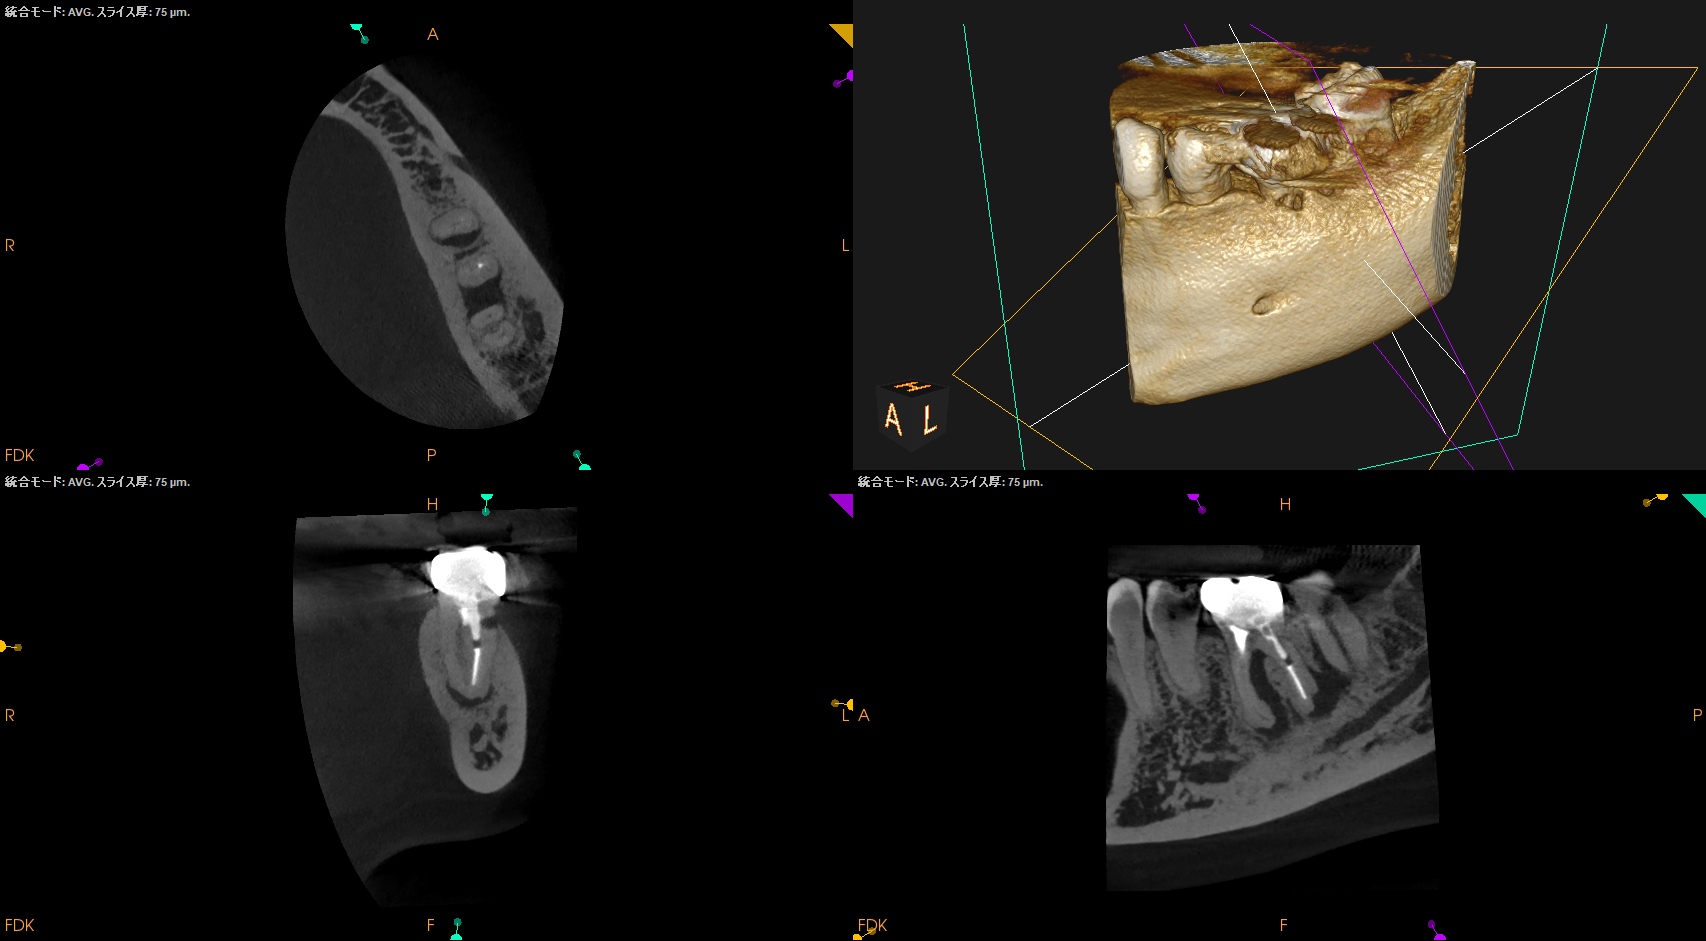

術後にPA, CBCTを撮影した。

MB

ML

DB

DL

B

問題はないだろう。